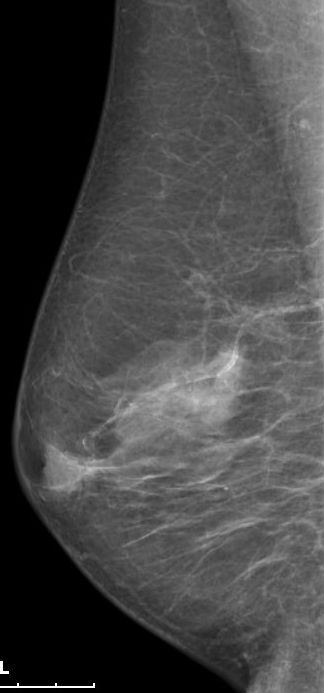

| Mammographie | 76-jährige Patientin mit multiplen Metastasen in Wirbelsäule und Leber. Zunächst kein Tastbefund der Brust. Dann suspekter Tastbefund rechts oben außen paramamillär. Mammographie zunächst o.B. befundet. Stanzbiopsie rechts oben außen: lobuläres Karzinom. | |||||||||